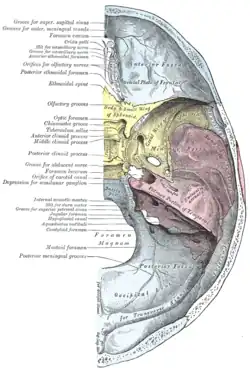

Left temporal bone. Inner surface. Base of the skull. Upper surface.

Base of the skull. Upper surface. Distribution of the maxillary and mandibular nerves, and the submaxillary ganglion.